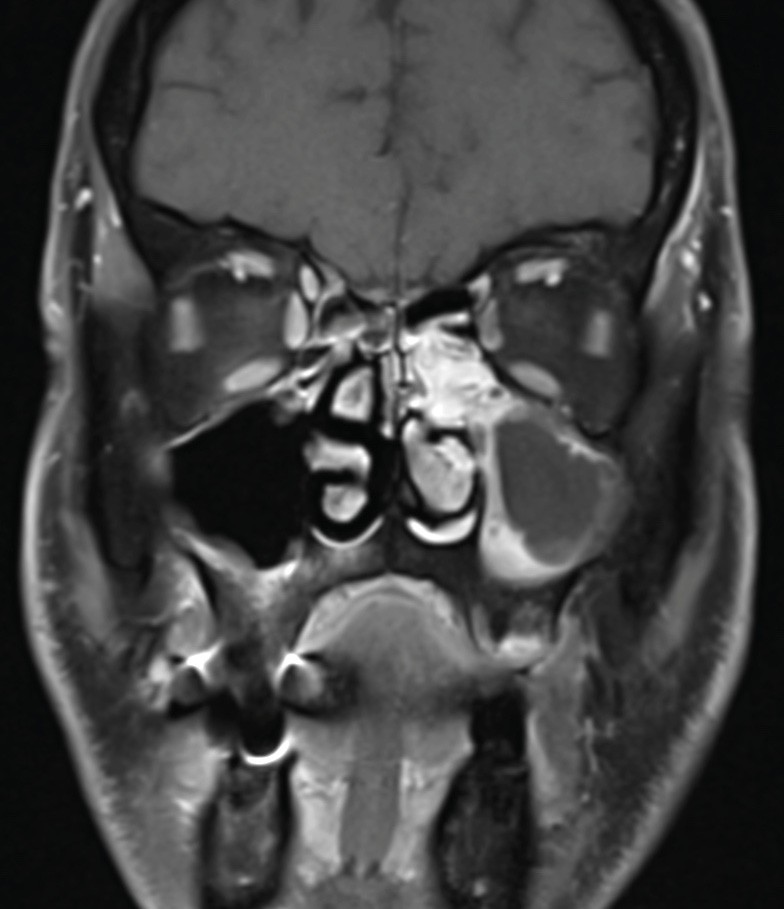

La tomodensitométrie des sinus retrouve un comblement complet unilatéral du sinus maxillaire gauche et des cellules ethmoïdales antérieures homolatérales, sans image de densité calcique intrasinusienne et sans lyse osseuse des parois (fig. 1). L’IRM montre un épaississement tissulaire de 23 mm de grand axe en regard du méat moyen gauche, avec un aspect de signal T2 hétérogène (fig. 2) et prenant le contraste en masse (fig. 3). Le comblement maxillaire gauche associé à un épaississement muqueux en cadre rehaussé correspond à une rétention en hypersignal en diffusion (fig. 4), avec diminution du coefficient apparent de diffusion (moyenne à 433 mm2/s) en faveur d’une pyocèle (fig. 5).